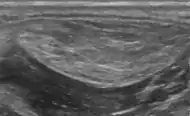

Medical ultrasonography of a lipoma in the thenar eminence: It is hyperechoic compared to adjacent muscle, and relatively well-defined, with miniature hyperechoic lines.[23]